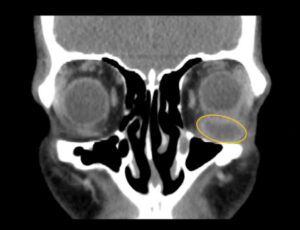

Inferior Rectus Abscess CT Coronal Annotated. JETem 2025